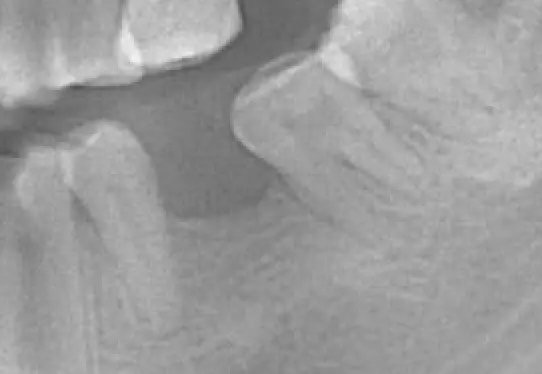

下方是患者初診的照片。患者有嚴重的咬合不正,但是基於身體條件,不適合進行齒顎矯正。下顎左側的缺牙使得她原本就不好的咬合功能變得雪上加霜,吃東西變得更困難。

下方是治療完成的照片。歷時四個多月,在患者、家屬、及醫療團隊的共同努力下,終於完成新的假牙製作。